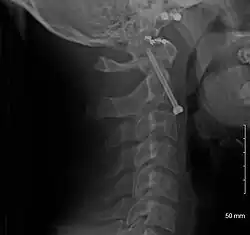

A fracture of the base of the dens as seen on plain X-ray -

A fracture of the base of the dens as seen on CT -